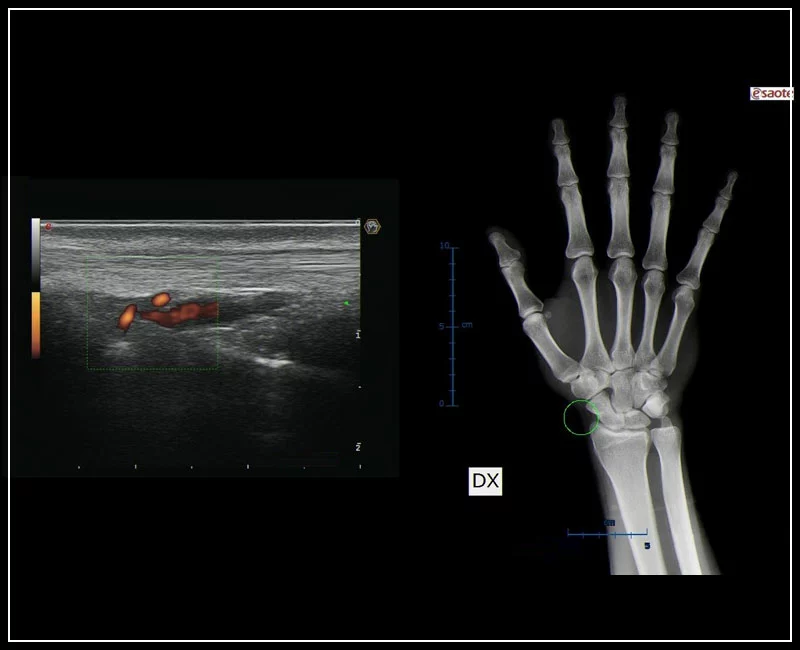

MyLab™9 Platform - MSK BodyMap and real-time XFlow on X-Ray extremities

MyLab™9 Platform - MSK BodyMap and real-time XFlow on X-Ray extremities